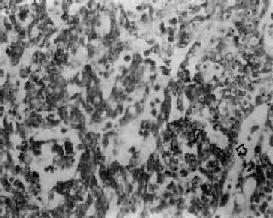

(4)未分化癌:癌细胞小而泡浆少,呈圆形或梭形,核圆形或卵圆形、浓染,细胞呈弥漫浸润,无明显癌巢形成。有时,癌组织主由短梭形细胞组成,颇似燕麦细胞癌(图9-7)。

图9-7 鼻咽未分化癌

癌细胞呈短梭形,核卵圆,浓染,呈燕麦细胞型癌结构